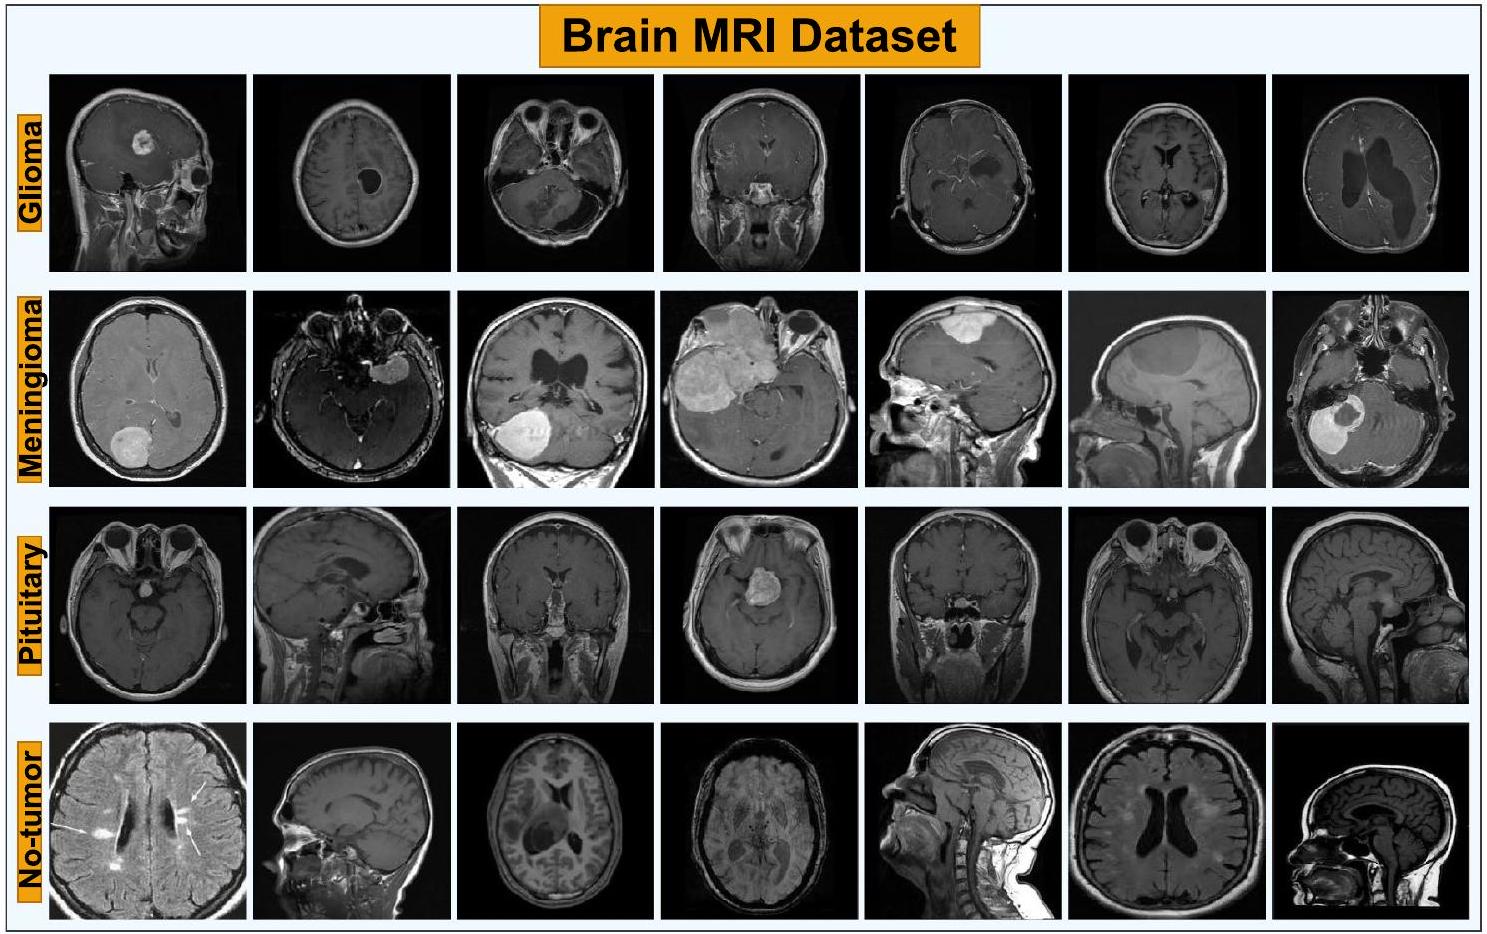

and make precise predictions on unobserved data with a sizable and representative dataset. Ensuring high-quality data is essential to address biases, reduce overfitting or underfitting issues, and improve performance across different subsets. For the autonomous classification of low-grade brain MRI images, several publicly available datasets exist, including Figshare [53], SARTAJ [54], and Br35H [55], which are known to be small-scale datasets. However, in this study, we utilized a publicly accessible brain MRI dataset shared on Kaggle [56], which combines and incorporates these three datasets to reveal the true capabilities of deep learning models on this task. Sample images from this dataset depicting both tumor and healthy cases are illustrated in Fig. 1.

وإجراء توقعات دقيقة على البيانات غير المرصودة مع مجموعة بيانات كبيرة وتمثيلية. إن ضمان جودة البيانات العالية أمر ضروري لمعالجة التحيزات، وتقليل مشاكل التكيف الزائد أو الناقص، وتحسين الأداء عبر مجموعات فرعية مختلفة. من أجل التصنيف الذاتي لصور الرنين المغناطيسي منخفضة الدرجة، توجد عدة مجموعات بيانات متاحة للجمهور، بما في ذلك Figshare [53] وSARTAJ [54] وBr35H [55]، والتي تُعرف بأنها مجموعات بيانات صغيرة الحجم. ومع ذلك، في هذه الدراسة، استخدمنا مجموعة بيانات الرنين المغناطيسي للدماغ المتاحة للجمهور والتي تم مشاركتها على Kaggle [56]، والتي تجمع وتدمج هذه المجموعات الثلاث لإظهار القدرات الحقيقية لنماذج التعلم العميق في هذه المهمة. يتم توضيح صور عينة من هذه المجموعة التي تصور كل من حالات الورم والحالات الصحية في الشكل 1.